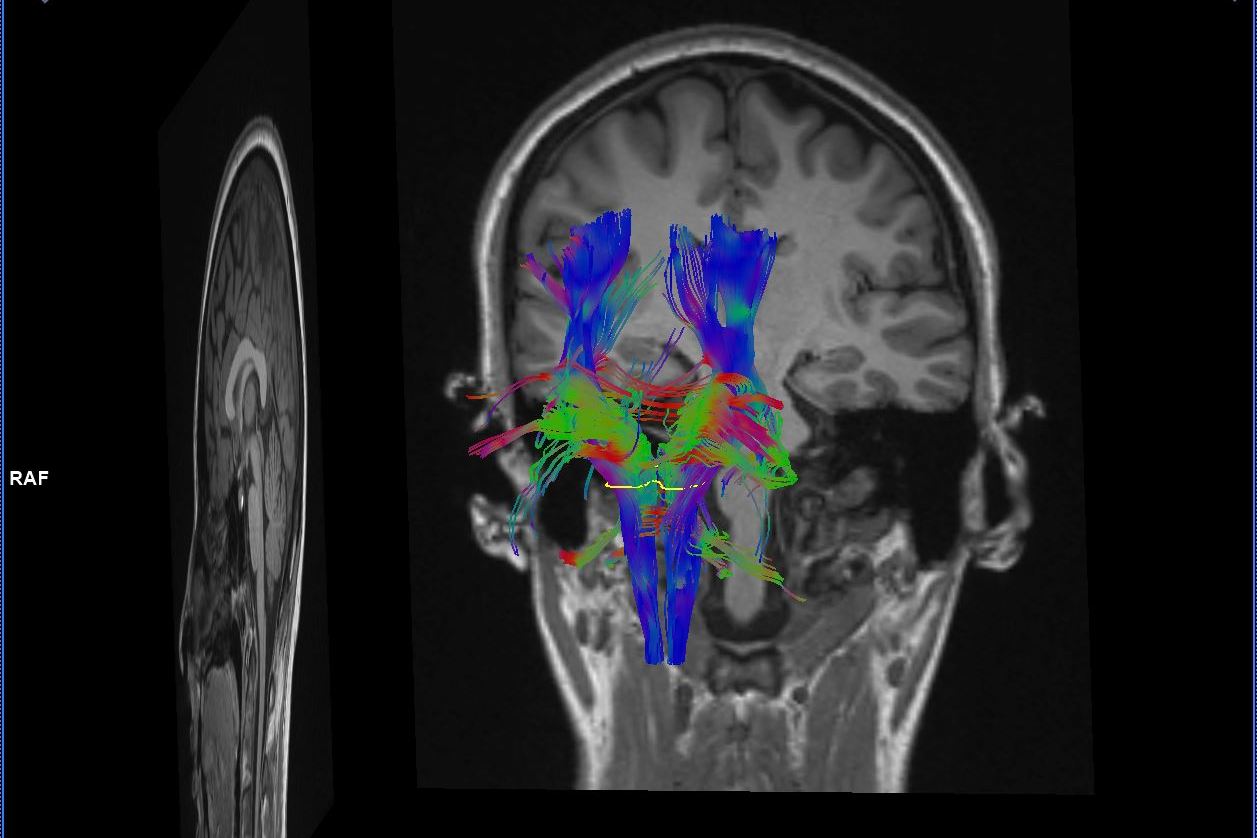

В Перинатальном центре НМИЦ им. В. А. Алмазова установлен современный сверхвысокопольный магнитно-резонансный томограф экспертного класса Magnetom Espree 1,5 Тесла (SIEMENS, Германия), позволяющий выполнять обследование беременных женщин (МРТ плода), детей любого возраста, проводить функциональные исследования головного мозга (фМРТ), а также все традиционные МР-исследования. |

В отделении магнитно-резонансной томографии перинатального центра проводятся исследования: